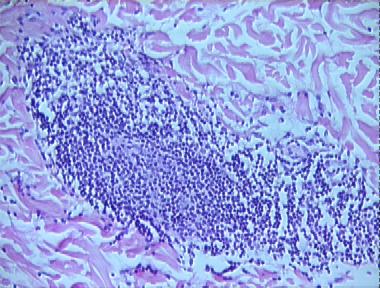

lymphocytic infiltration of Jessner

Histologic Features